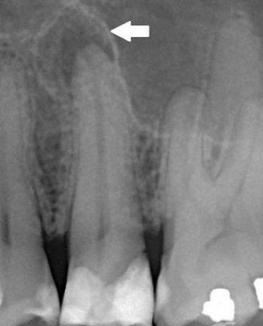

Периодонтитът е възпаление на тъканите около корена на зъба (периодонциума). Той се развива най-често от нелекуван пулпит.

При хроничен периодонтит пациентът усеща тъпа болка при дъвчене или може да няма оплаквания. Често проблемът се открива случайно на рентгенова снимка. В даден момент е възможно хроничният процес да се обостри.